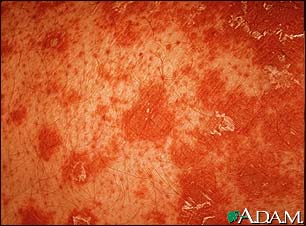

Pityriasis rubra pilaris (PRP) is a rare skin disorder that causes inflammation and scaling (exfoliation) of the skin.

PRP is a chronic skin condition in which orange or salmon-colored scaly patches with thick skin develop on the hands and feet.

The scaly areas may cover much of the body. Small islands of normal skin (called islands of sparing) are seen within the areas of the scaly skin. The scaly areas may be itchy. There may be changes in the nails.